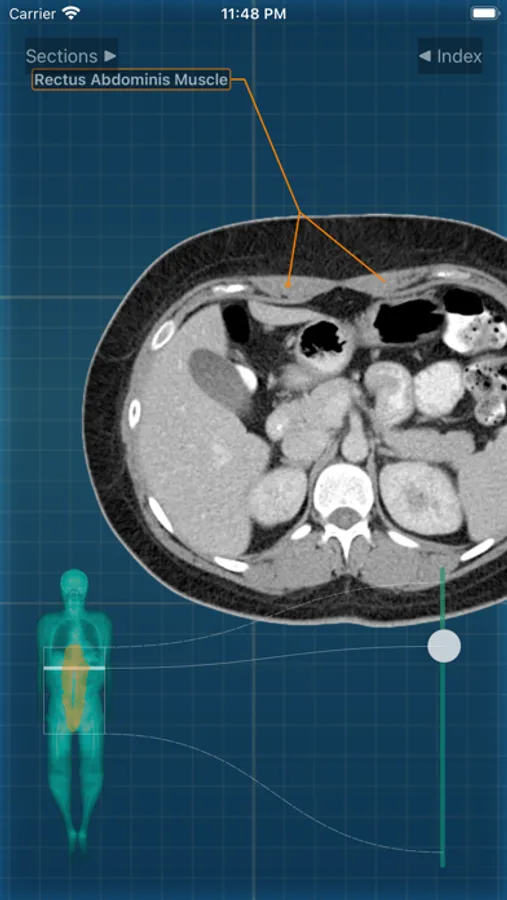

X-Anatomy is a transaxial cross-sectional human anatomy interactive medical imaging atlas using CT images, designed for medical professionals & all students of anatomy.

* Includes hundreds of images from actual human patient body scans.

* Use the intuitive BODY LOCALIZER to show you where you are as you scroll through the body, as well as the general region of the anatomic structure

INCLUDED body section modules cover the major body sections from head to pelvis: CT Brain, CT Neck, CT Sinuses, CT Chest, CT Lungs, CT Abdomen & Male Pelvis, CT Abdomen & Female Pelvis.